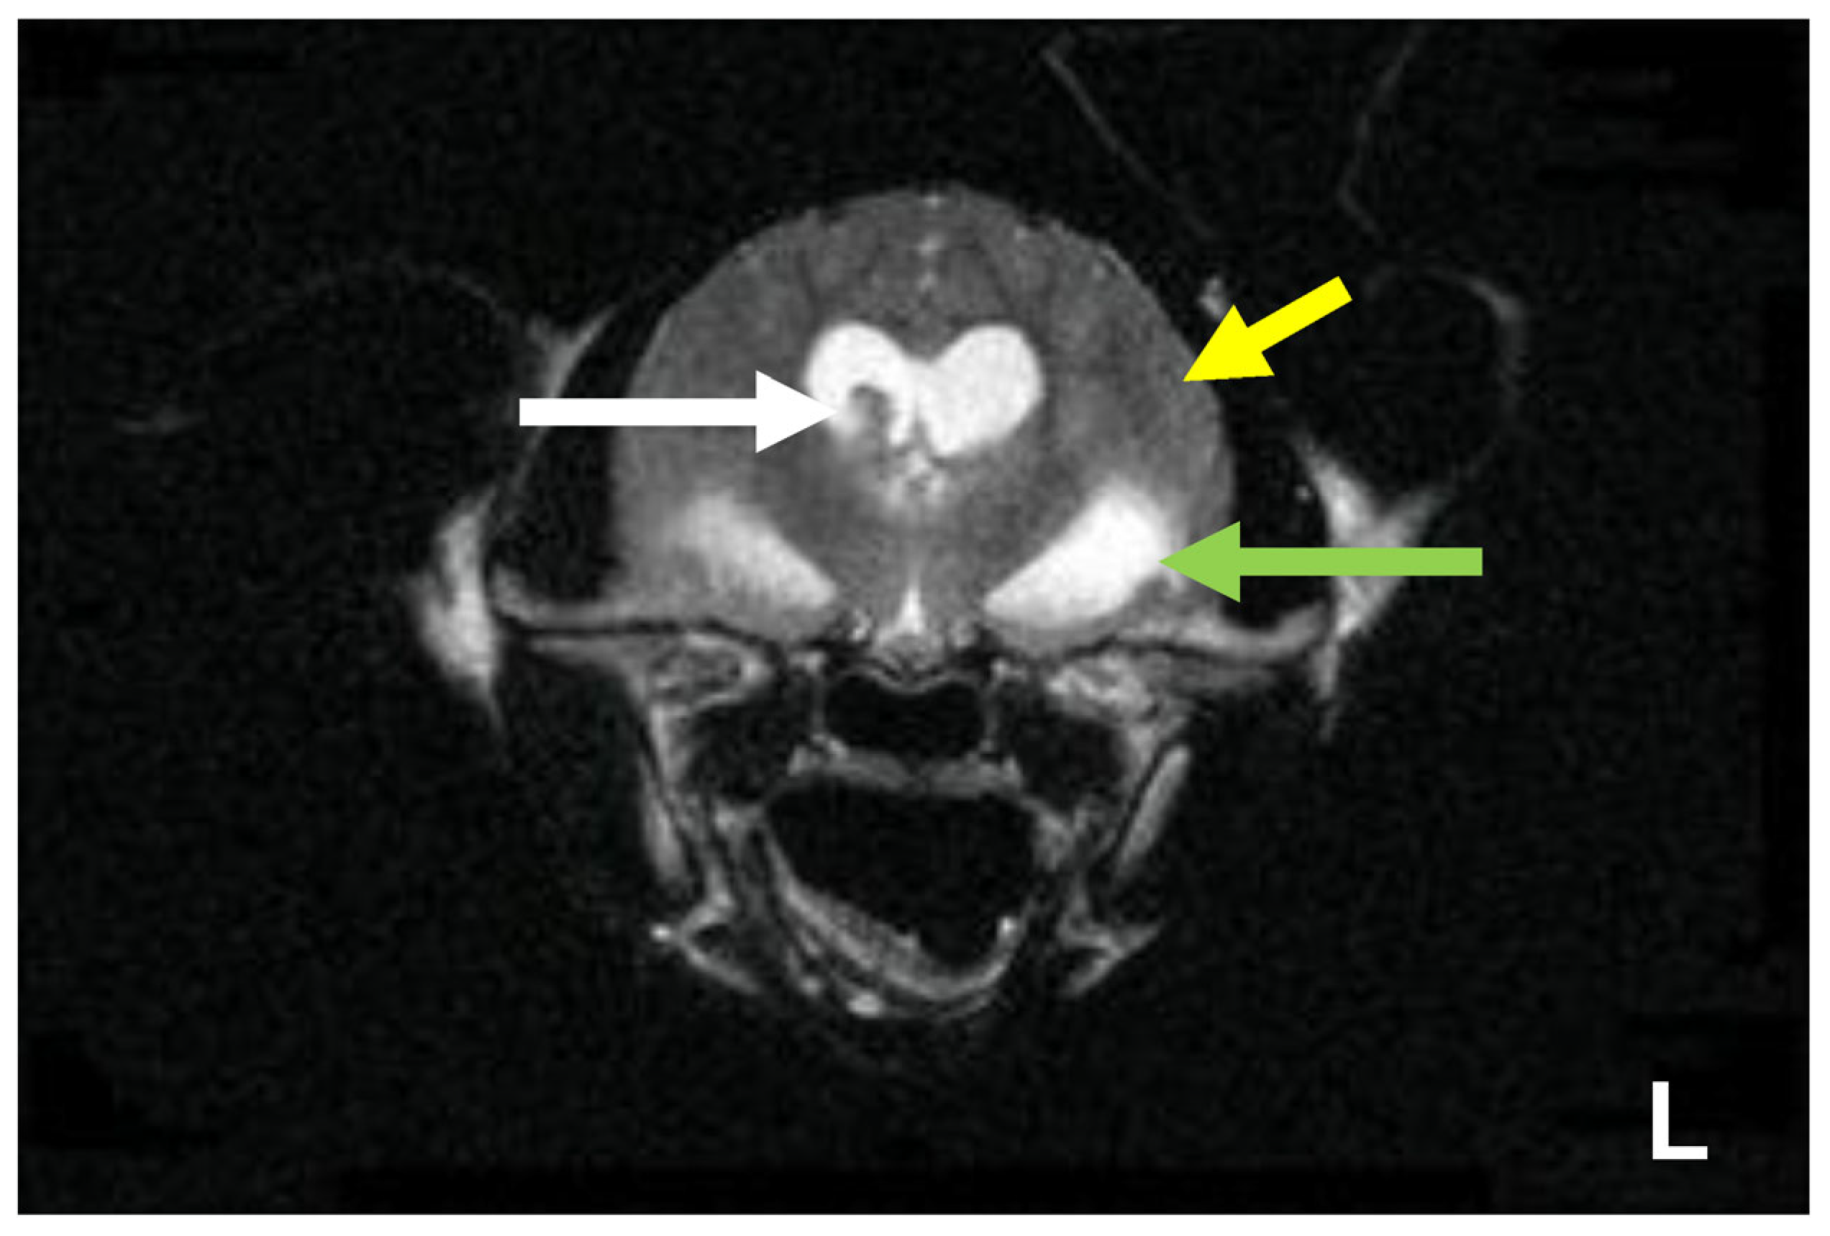

7.4.2. Advanced Imaging of the CNS: MRI and CT

| Summary of Section 7: Diagnosis of FIP; Section 7.4: Diagnostic imaging in FIP: No specific ultrasonographic or radiographic findings exist for FIP. Ultrasonography (in particular) and radiography can show the presence of effusions. Pneumonia due to FIP that is occasionally reported can be associated with radiographic changes. Ultrasonography can reveal abdominal lymphadenomegaly or lymphadenopathy and/or abnormalities of the liver, spleen, intestines and/or kidneys (which can include a medullary rim sign), depending on which organs are affected. Imaging can also be of use to the direct sampling of abnormal tissues, e.g., fine-needle aspirate for cytology examination to reveal non-septic pyogranulomatous inflammation, or ultrasound-guided needle core (e.g., tru-cut) biopsies can be collected and submitted for histopathology. When a cat is showing neurological signs, the imaging of the brain by magnetic resonance imaging, if available, with contrast, can be useful to demonstrate neurological abnormalities (such as obstructive hydrocephalus, syringomyelia, foramen magnum herniation and marked contrast enhancement of the meninges, third ventricle, mesencephalic aqueduct, and brainstem). A description of computerised tomography findings in cats with neurological FIP has not been published, but MRI is likely to be more sensitive in the detection of subtle intraparenchymal lesions. Advanced imaging of the central nervous system is indicated before performing cerebrospinal fluid sampling to assess the potential risk of herniation. |